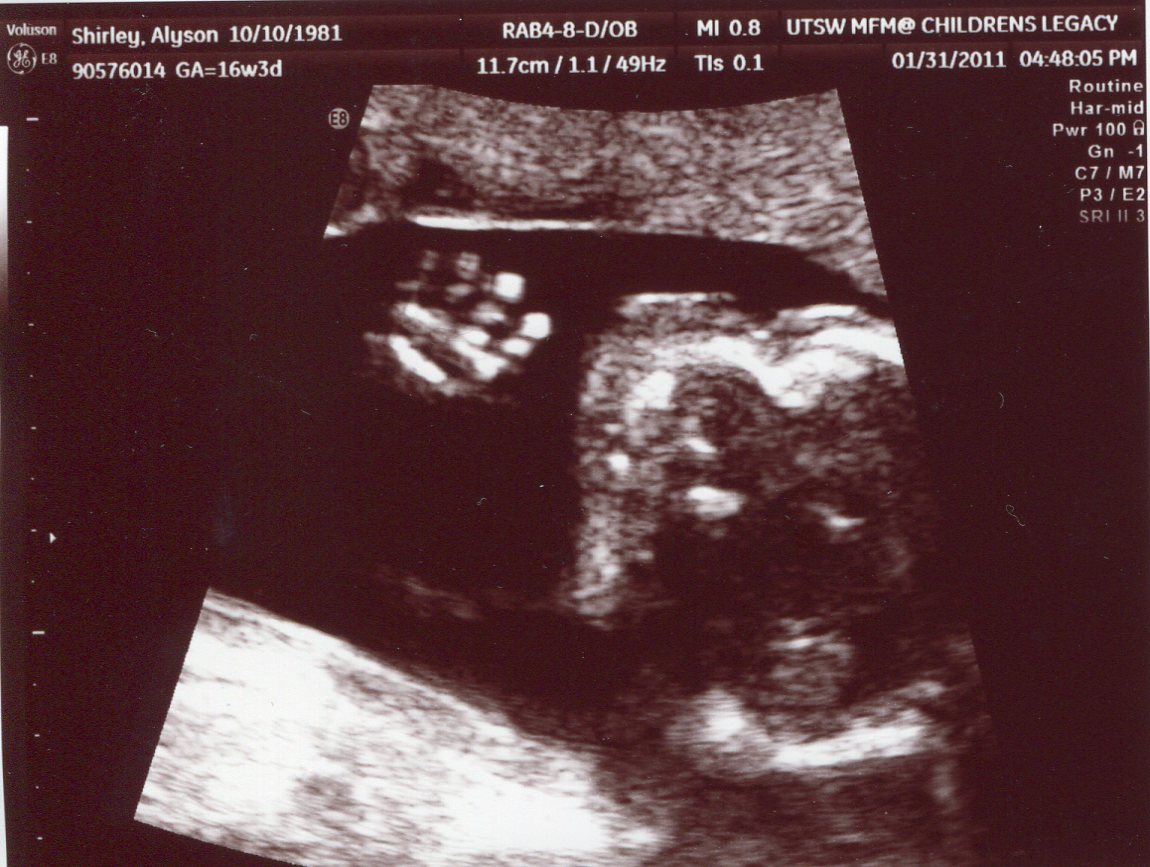

Announcing Twin Shirley boys!!

At our 2nd appointment with the specialist today, we found out for sure that they are both boys. It was very evident from the ultrasound today, even Zach and I could tell for sure. Thankfully, they were both cooperating!